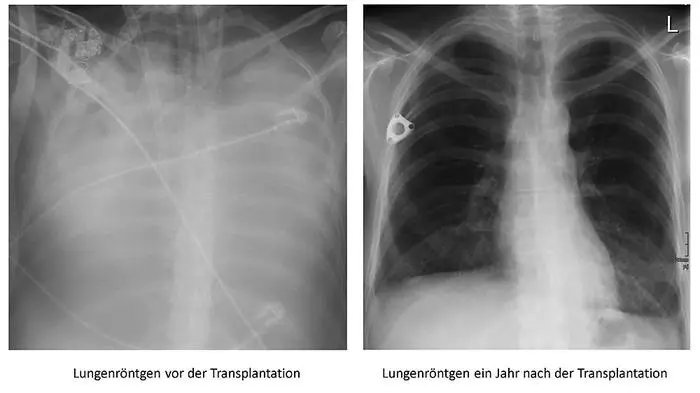

Sabine V. (45) wäre im Vorjahr fast an Corona gestorben. Eine Lungentransplantation im AKH Wien, damals die erste an einer Corona-Erkrankten in Europa, rettete der Kärntnerin das Leben. Erstmals spricht sie über ein „echt hartes Jahr“ und wie sie sich wieder ins Leben gekämpft hat.

Die Lunge der Kärntnerin vor der Operation (links) und danach